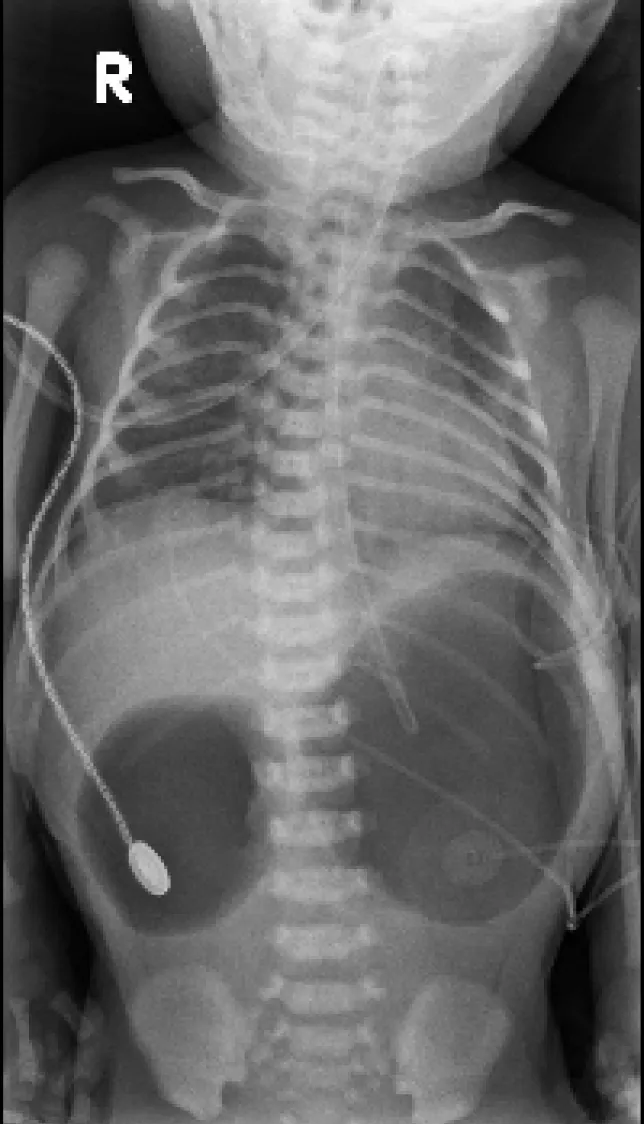

【113-1 醫學(五) 第44題】

一幼兒因嘔吐求診,腹部X光如圖所示,下列何者為最不可能之鑑別診斷?

破題關鍵

這張腹部X光片最明顯的特徵是「雙氣泡徵」(double bubble sign),這表示消化道阻塞發生在十二指腸或其近端,因此要找出最不可能造成這種阻塞的病因。